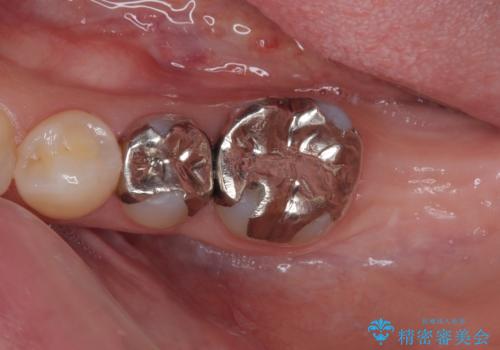

歯肉が腫れてズキズキする 奥歯の根管治療